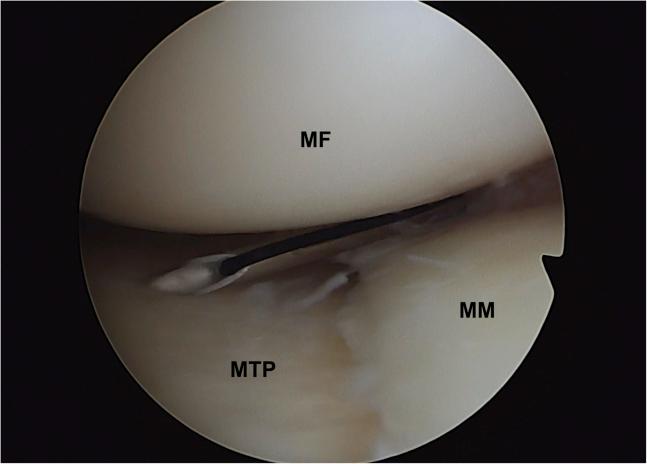

Medial meniscal sutures using outside-in or inside-out techniques are very popular. Nevertheless, a saphenous nerve entrapment may occur with these techniques. This Technical Note describes a modified outside-in medial meniscus suture without any additional skin incisions. By dissecting the space between the subcutaneous and the capsule, which is performed by grasping and knotting the sutures through the anteromedial portal, iatrogenic saphenous nerve injury is avoided.

使用由外向内或由内向外技术进行内侧半月板缝合非常普遍。然而,这些技术可能会导致隐神经卡压。本技术说明描述了一种改良的由外向内内侧半月板缝合方法,无需额外的皮肤切口。通过在皮下组织和关节囊之间进行解剖,这是通过经前内侧入路抓取和打结缝线来完成的,从而避免了医源性隐神经损伤。